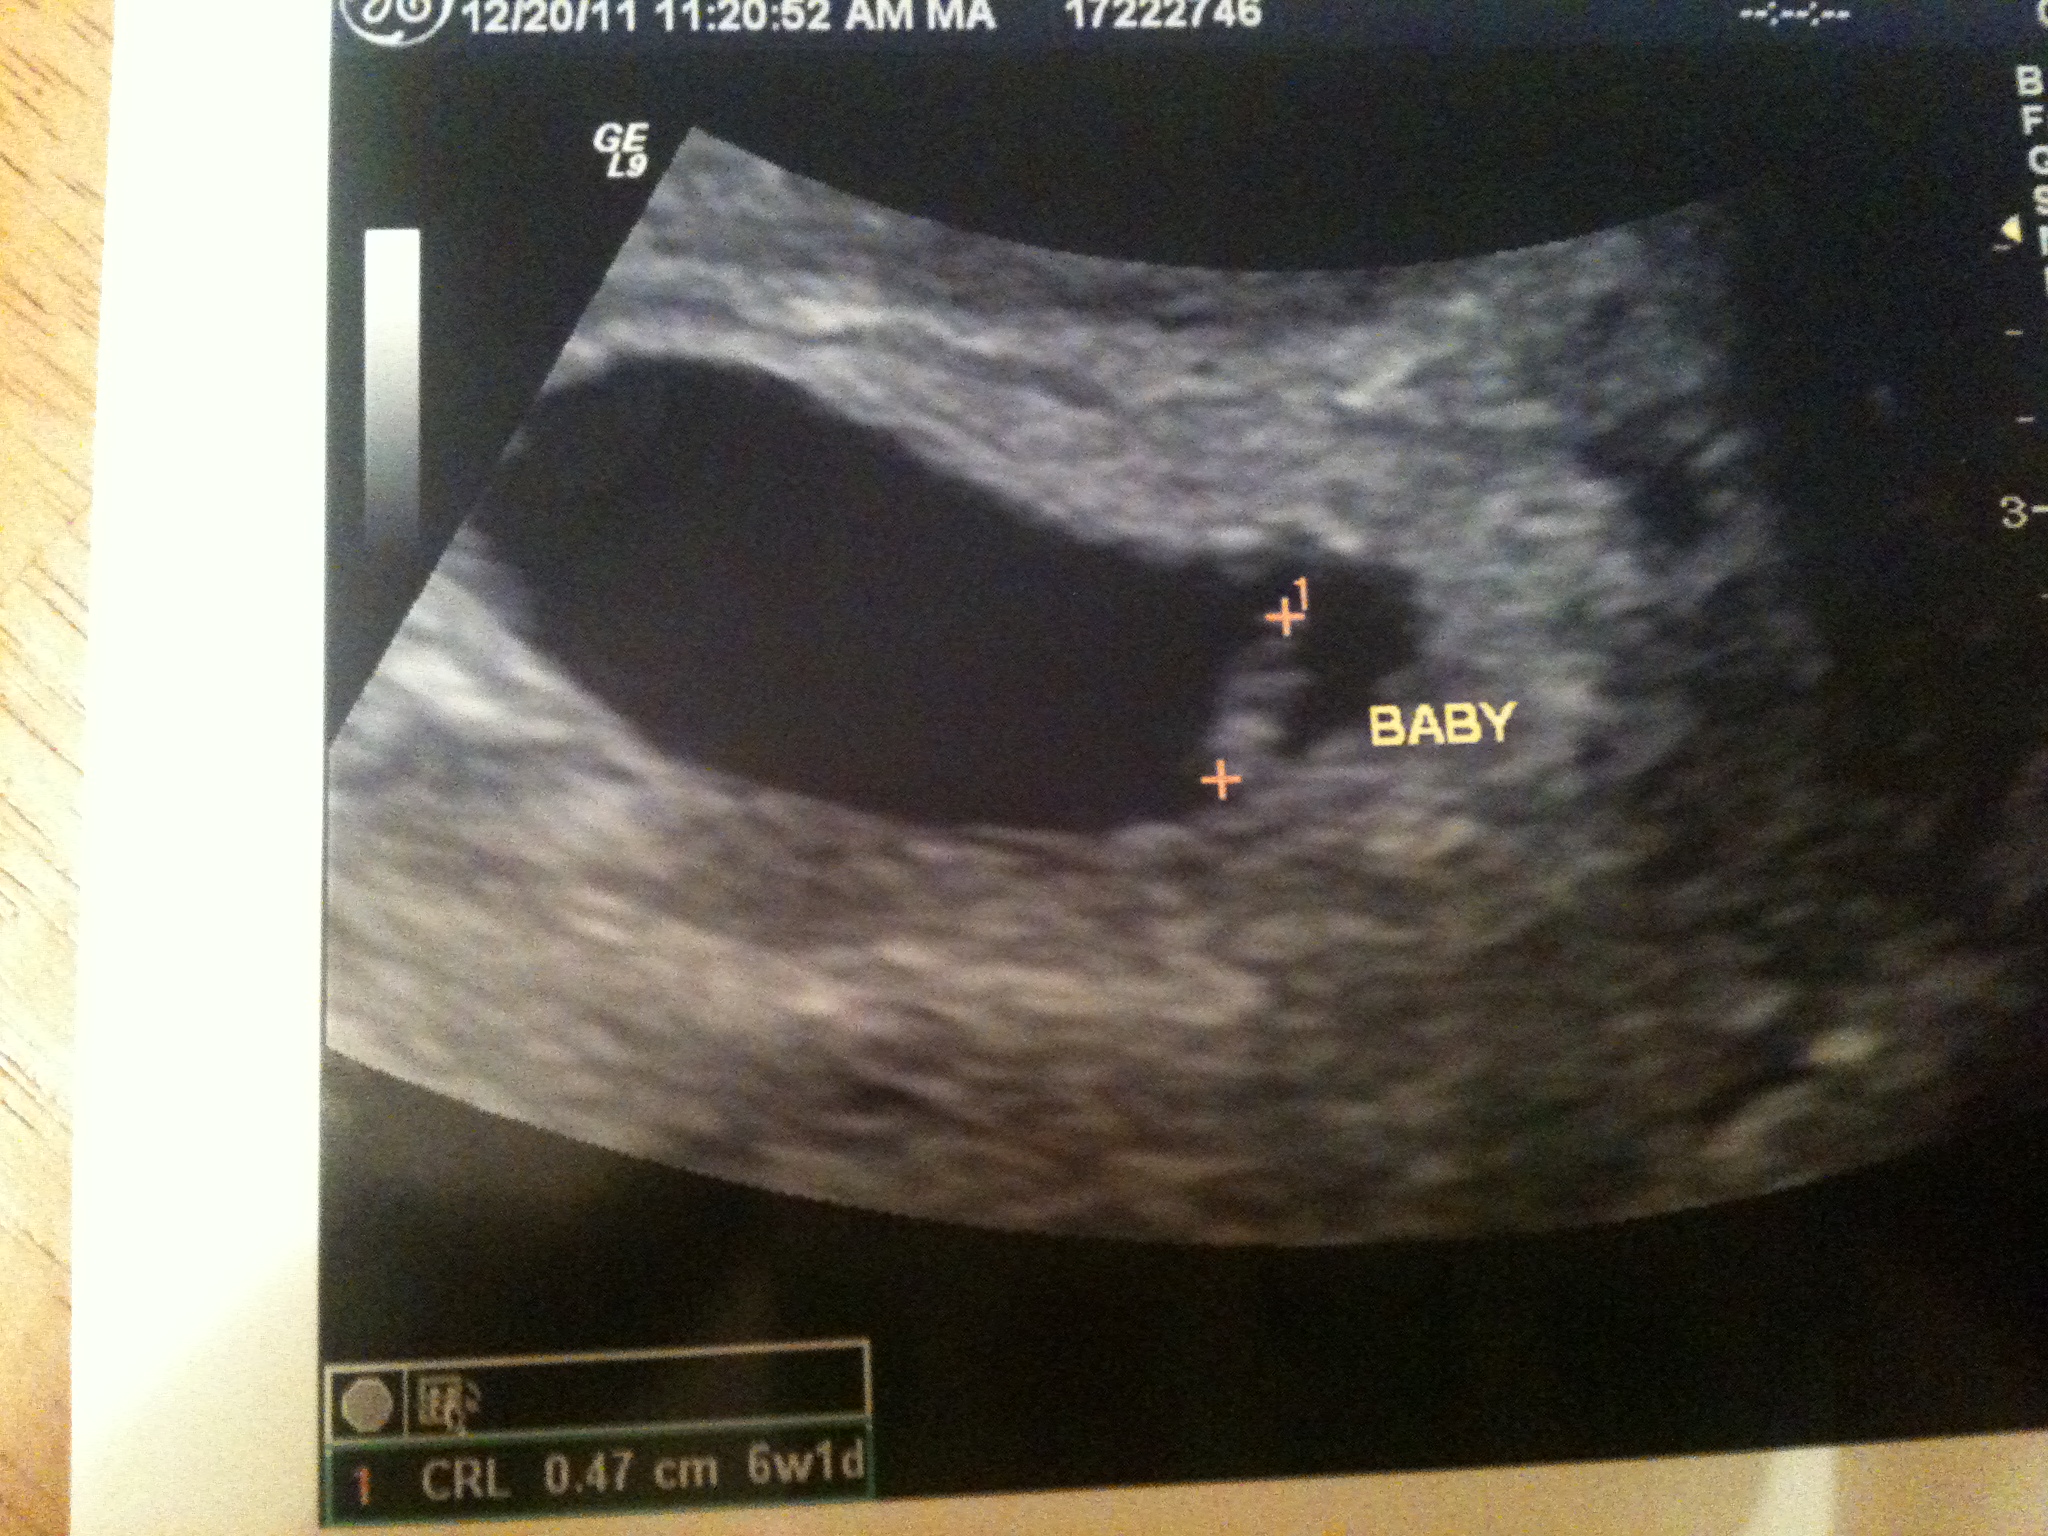

December 20th – Keith and Punky are off to Punky’s very first field trip…and Mama has a second ultrasound. Super scared as I soooooo needed to see a heartbeat so that I knew we weren’t repeating March 2008. This ultrasound technician was AWESOME. She showed me everything, took measurements, and gave me pictures of “that piece of rice!” Heartbeat was 123 beats/minute. Perfect! 6 weeks along…